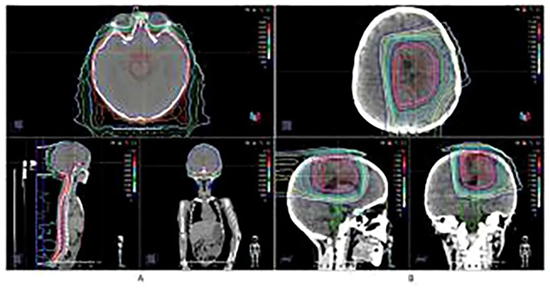

河北一洲肿瘤医院成功完成罕见儿童脑瘤治疗,成果论文登上国际知名期刊

星形母细胞瘤(Astroblastoma),是一种极为罕见的颅内胶质瘤,在2021年世界卫生组织(WHO)的分类中,其MN1基因异常型被正式确立。